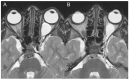

Results: A 6-year-old patient was admitted for right otomastoiditis and thrombosis of the sigmoid and transverse sinuses, as well as the proximal portion of the internal jugular vein. Radiological examinations revealed a left orbital mass (22 × 14 mm) compatible with asymptomatic orbital meningocele (MC) herniated from the superior orbital fissure (SOF). The child underwent a right mastoidectomy. After the development of symptoms and signs of intracranial hypertension (ICH), endovascular thrombectomy and transverse sinus stenting were performed, with improvement of the clinical conditions and reduction of the orbital MC. The systematic literature review encompassed 29 publications on 43 patients with spontaneous orbital MC. In the majority of cases, surgery was the preferred treatment.